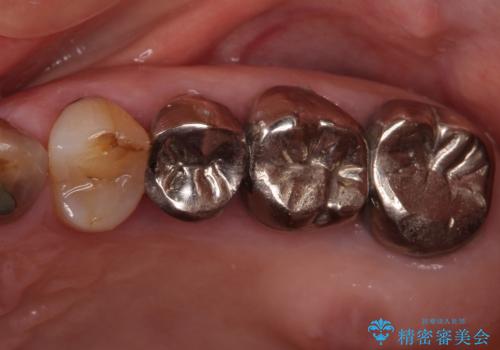

全ての奥歯の銀歯をセラミックに メタルフリー治療

- 奥歯に装着されている銀歯を全て外したいとのことで来院された患者様です。

土台に含まれている金属も含め、奥歯の金属は全て除去し、オールセラミッククラウンやセラミックインレーにて治療することとしました。